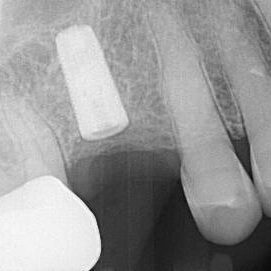

ULTRASONICS: Complications of Abutment Screw Retrieval Secondary to Prior Ultrasonic Attempts

There has been much written on the use of ultrasonics in retrieving fractured screw fragments, which I didn’t think a lot about until May of 2023, as it has not been a part of my fractured screw retrieval algorithm.